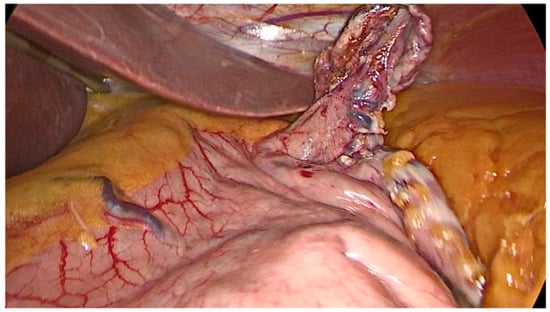

- After the transoral position of a bougie (of diameter ranging 36–40 Fr), sleeve gastrectomy is performed with the use of a stapler, beginning from the distance of 4–6 cm from the pylorus up to the angle of His.

- Care must be taken in the first two uses of the stapler to prevent narrowing the gastric sleeve at the incisura.

- Symmetric traction on the anterior and posterior stomach wall must be undertaken during stapling.

- The staple line should be regular and straight from the antrum to the angle of His.

- The staple line should stay at least 1 cm away from the esophago-gastric junction.